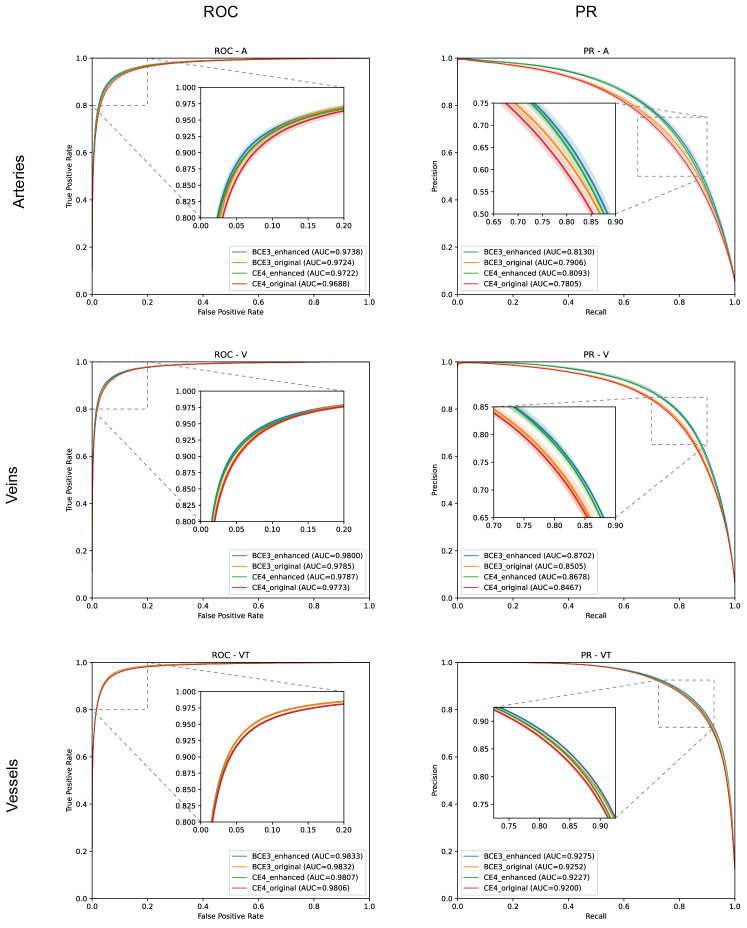

In Figure 8, the mean ROC and PR curves in RITE-test for the networks that were trained using the BCE3 and CE4 losses with and without image preprocessing (“enhanced” and “original”, respectively) are depicted.

As commented in the previous sections, we include three ROC and PR curves, one for each structure of interest: arteries (A), veins (V), and Vascular Tree (VT)—that is, vessels—. Figure 9 depicts the ROC and PR curves for the different networks in the DRIVE-test set.

Additionally, all AUC values of the curves are summarized in Table 2.

As it can be observed in the vasculature segmentation results of Figures 8 and 9 as well as Table 2, the best performance is achieved by the proposed MS approach using the BCE3 loss, either using the enhanced or the original retinography as input, and regardless of the target class. For each structure of interest, i.e. arteries, veins and vessels, both the AUC-ROC and AUC-PR values are higher with the MS approach than with the traditional CE4 one. Furthermore, AUC-PR and AUC-ROC for vessels are significantly higher for the MS approach than for CE4 (), as well as other statistics like AUC-ROC for arteries () and AUC-ROC por veins ().